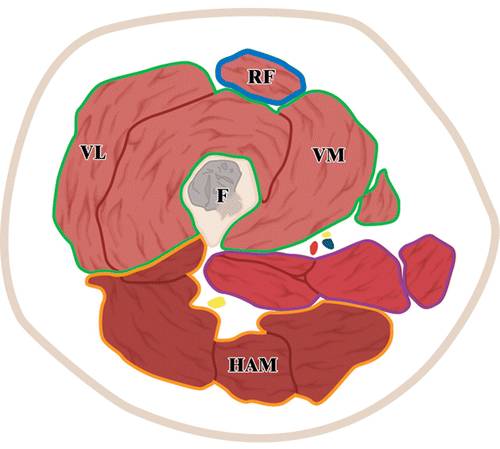

9 -大腿轴向图